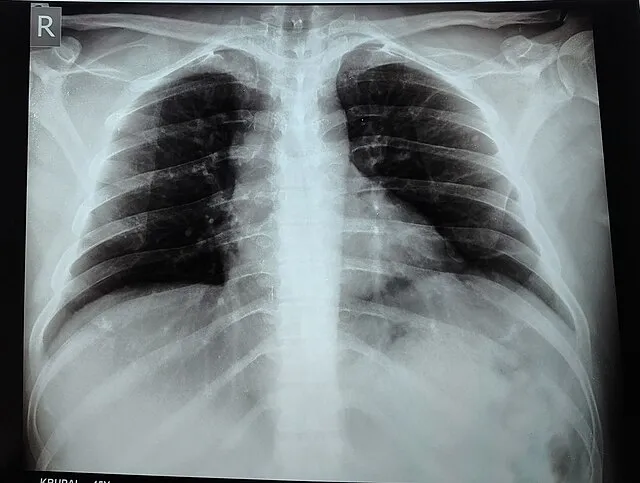

2. 2. X-rays

Wikibantu on wikimedia

Wilhelm Conrad Roentgen discovered X-rays while experimenting with cathode rays in 1895. He noticed a glowing effect on a nearby screen, indicating an invisible type of radiation passing through objects. His accidental observation led to the creation of medical imaging, allowing doctors to see inside the body without surgery. The discovery quickly became an essential diagnostic tool.